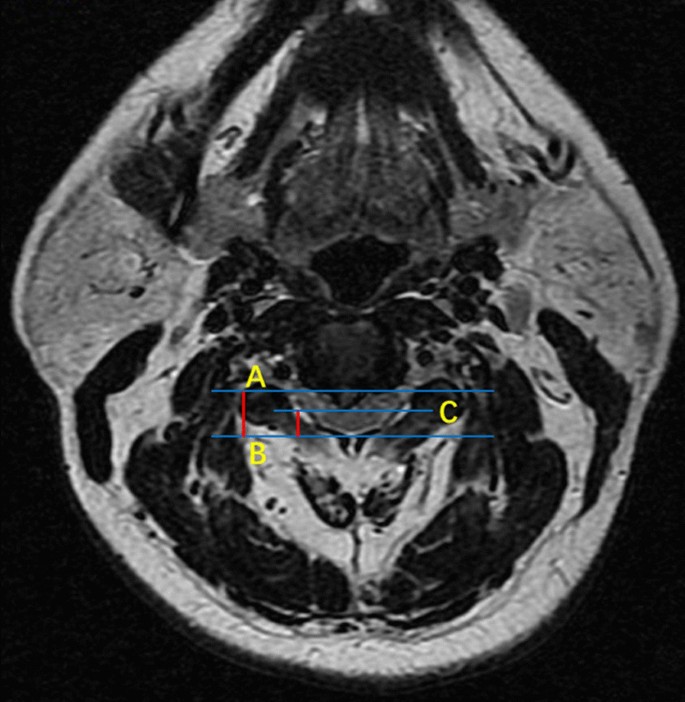

The mean time of surgery in this study was 120.3 min which was chosen as the cut-off. Operation time longer than 120 min or intraoperative blood loss equal to or greater than 200 ml was considered as a high-difficult surgery. Otherwise, it was defined as low-difficulty surgery. Examined radiological parameters included high signal intensity of spinal cord on T2-weighted images, OPLL, sagittal cervical circumference, coronal cervical circumference, cervical length, anteroposterior diameter of the spinal canal, the shortest diameter of the spinal canal, and spinal canal occupational ratio. Sagittal and coronal cervical circumferences were defined as the distance between the intersection of the line parallel to the endplate through the midpoint of C5 and soft tissue shadow (Fig. 1). Cervical length was measured as the distance between the sternum and gnathion on the lateral radiograph (Fig. 1a). The anteroposterior and shortest diameter of the spinal canal were measured at the most compressed level using standard picture archiving and communication system (PACS). Anteroposterior diameter was the distance between the posterior edge of the vertebral body and spinal canal while the shortest diameter was defined as the distance between the posterior edge of the compression and spinal canal. The following formula was used to calculate the spinal canal occupational ratio: spinal canal occupational ratio = (anteroposterior diameter-shortest diameter)/anteroposterior diameter (Fig. 2).

At the most compressed level, the anteroposterior diameter was defined as the distance between the posterior edge of vertebral body and spinal canal (a, b). The shortest diameter was the distance between the posterior edge of compression and spinal canal (b, c). Spinal canal occupational ratio = (anteroposterior diameter-shortest diameter) / anteroposterior diameter